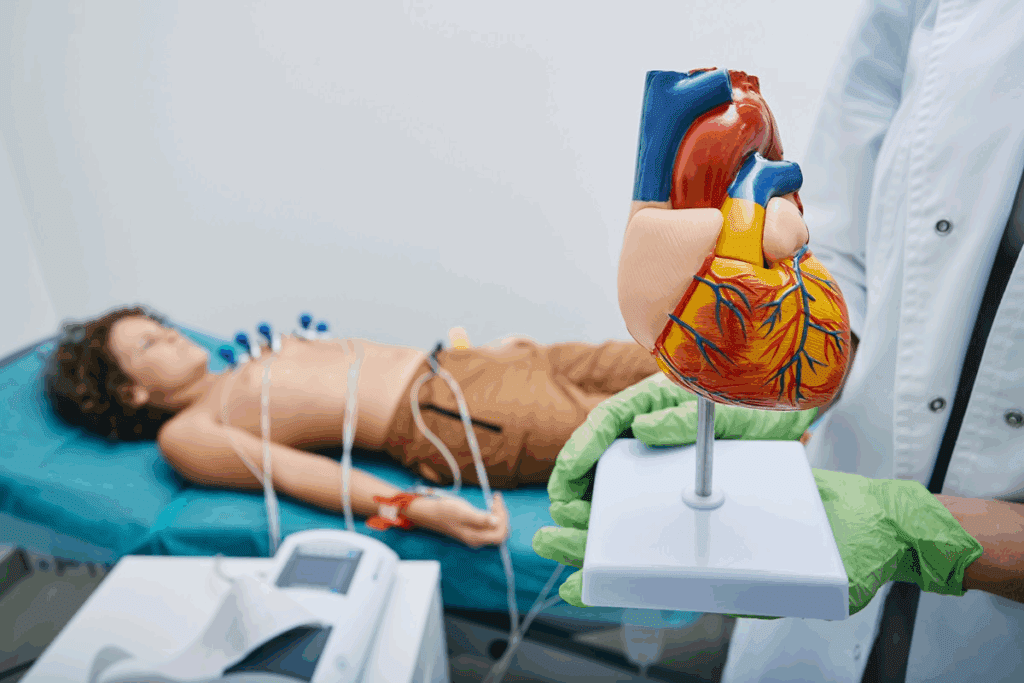

ECG third degree av block atrioventricular (AV) block, also known as complete heart block, is a serious heart condition. It stops electrical signals from the atria from reaching the ventricles. This makes the atria and ventricles beat on their own, a condition called AV dissociation.

This condition is very serious and needs immediate medical help. At Liv Hospital, we focus on top-notch heart care. Knowing the ECG signs of third-degree AV block is key for diagnosing and treating it.

Third-degree AV block, also known as complete heart block, is a serious heart condition. It needs immediate medical help. This condition causes AV dissociation, where the heart’s upper and lower chambers beat at different rates. This can lead to severe problems.

Definition and Pathophysiology

Third-degree AV block stops the electrical signals from moving between the heart’s upper and lower chambers. This means the chambers work on their own, leading to AV dissociation. The upper chambers beat normally, but the lower chambers beat slower, usually between 40-60 times per minute.

The heart’s electrical system is interrupted in third-degree AV block. This can happen for many reasons. These include heart damage, heart attacks, infections, and some medicines.